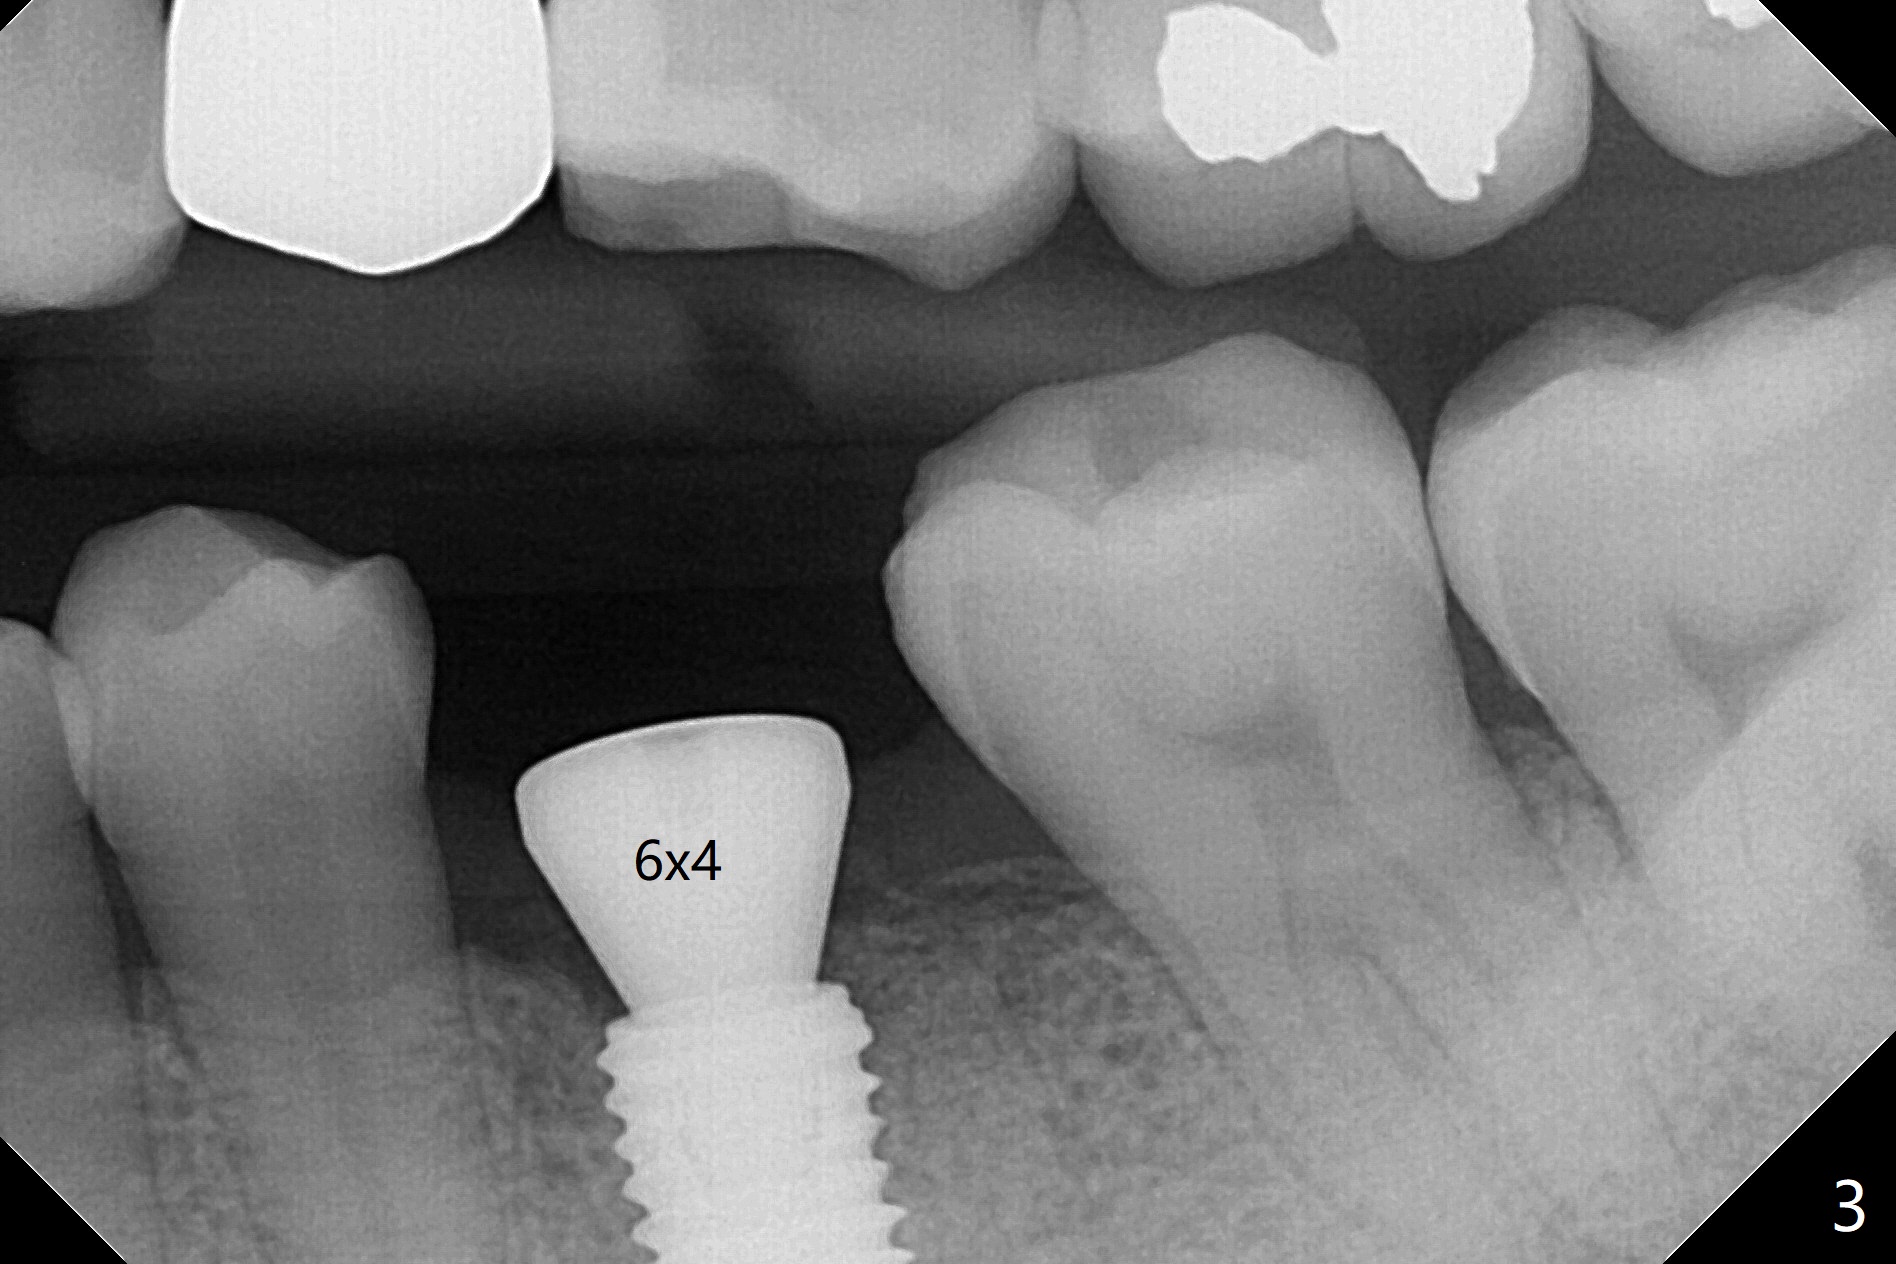

50来岁男,左下6位点保存术后4.5个月回来做导板植牙术,牙槽嵴和角化龈宽,几乎是最理想的手术。唯一担忧的是牙槽骨够不够硬(植骨后4.5个月),其实为了植入5毫米植体(图一),最后钻头必须4.5毫米,而且需要使用4.5毫米皮质骨功螺纹钻头,反复多次倒旋植体,最后扭力50Ncm,唯恐造成骨坏死。使用6毫米profile钻头后,放置6x4毫米基台,后者完全就位(图二,三)。术后病人汇报他根本感觉不到做过植牙术,以前做过徒手即刻植牙(30 13)。术后3.5月去除愈合基台,牙龈袖健康,使用Prosthetic treatment planning基台(没有六角形,容易就位,选择袖高度),放置修复基台(图四),拧紧20Ncm(厂家推荐30Ncm),放置plumber tape and Cavit,取模。口内粘固,事先牙冠(带有access hole)边缘涂凡士林,容易去除残余粘固剂,争取不取出基台,减少牙龈附着破坏。